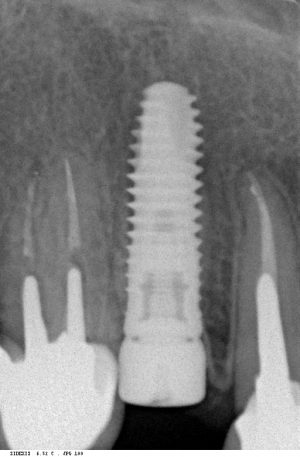

Мы сделали рентгеновские контрольные снимки —  панорамный для оценки положения имплантатов и прицельный для контроля посадки абатментов.

На последнем видно, что абатменты (особенно правого на фото зуба) не сели на свои места, между ними и платформами имплантатов есть щель — и эта ситуация наглядно демонстрирует, ПОЧЕМУ такие снимки необходимы. Мы вернули пациентку в хирургический кабинет и провели коррекцию абатмента (уменьшили ширину трансгингивальной части), После чего, проводили пациентку в кабинет стоматолога-ортопеда для временного протезирования.

Установка абатментов занимает 2 минуты.